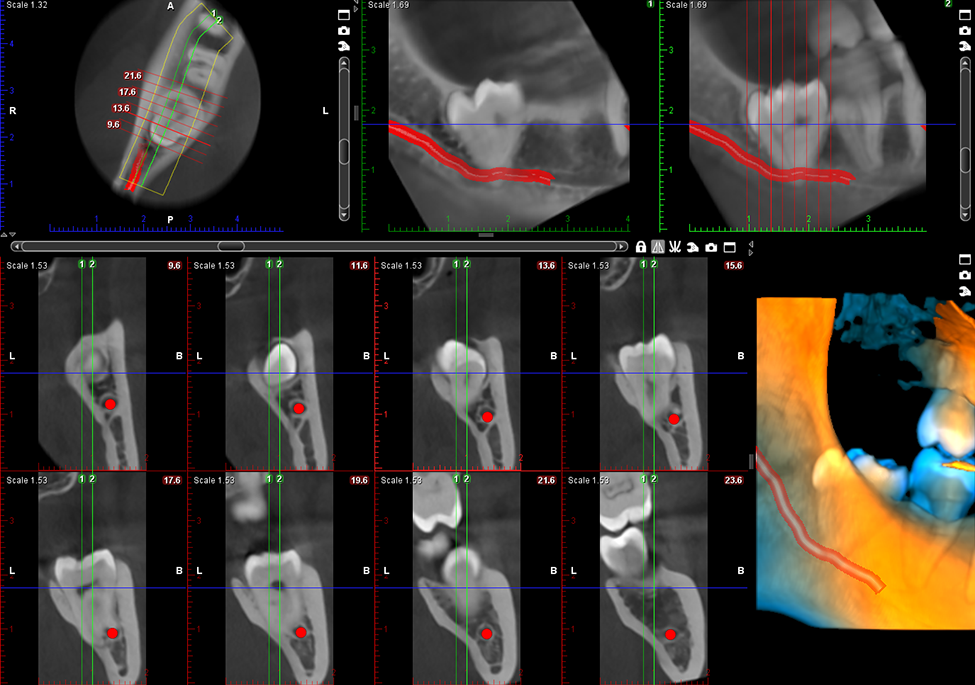

Wysokiej jakości obrazowanie endodontyczne

Jakość obrazu bez wątpienia ma ogromne znaczenie, jednak każdy obraz składa się z małych części. Oferowany przez nas tryb obrazowania endodontycznego jest idealny do wykonywania zdjęć małych szczegółów anatomicznych. Gwarantuje niezwykle wysoką rozdzielczość przy wielkości woksela wynoszącej 75 μm.

Obrazy Kliniczne Planmeca ProMax 3D Mid